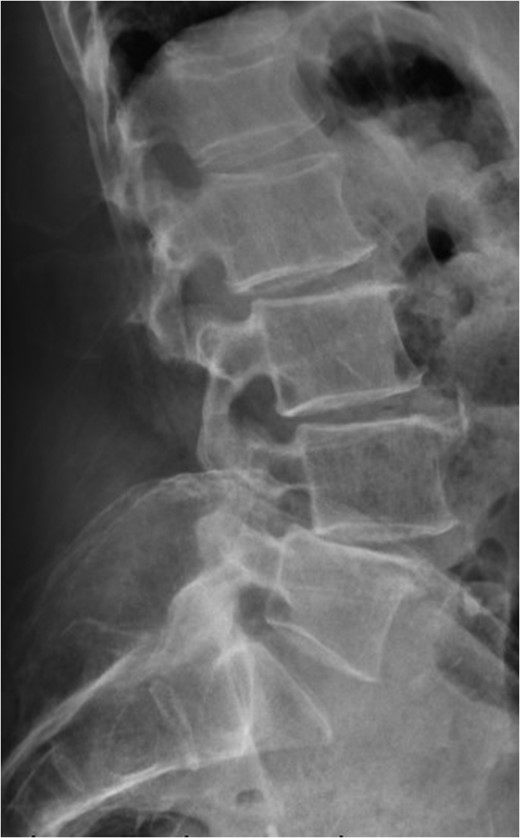

Standing lateral lumbar radiograph obtained 2 weeks following the patient's initial lumbar surgery (L3–S1 laminectomy). No instability is noted on the postoperative image.